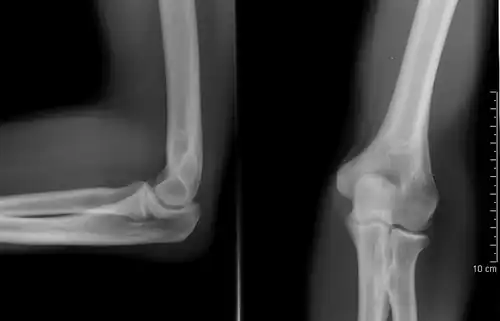

A plain radiograph of the elbow

AP radiograph of the lumbar spine